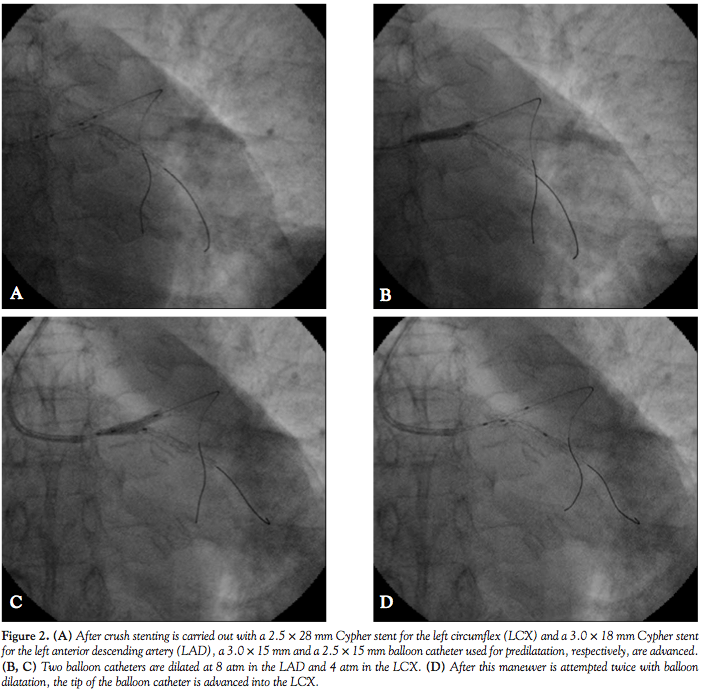

lesion for the final KBT. For those patients who did not undergo predilatation or received predilatation with a single balloon catheter, we produced new balloon catheter(s) for the final KBT. When the balloon catheter used for the side branch was stuck at the ostium of the LCX (Figure 1A), both balloons were inflated simultaneously with the LCX balloon catheter in a stuck position (Figures 1B and 1C). Inflation of the balloon catheter in the main branch was carried out at nominal or high pressure (usually at 8-12 atm) at the same time as the balloon catheter in the side branch was under nominal pressure (2-6 atm). This procedure changes the angle of the tip of the balloon catheter stuck in the side branch and widens the stent strut at the ostium of the LCX. After the balloon was inflated several times, it eventually crossed the stent strut (Figure 1D). When the buddy-balloon technique failed, a 1.5 mm balloon catheter was introduced into the LCX, and the same procedure was performed again until the balloon crossed the stent strut. Angiograms of a typical case are presented in Figure 2. Scheduled angiographic follow-up was conducted between 9 and 12 months after the index procedure.